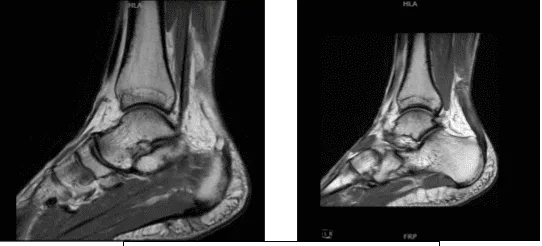

Se revisaron y discutieron las resonancias magnéticas, los tejidos blandos presentan hinchazón y edema posteriores significativos de tejidos blandos secundarios a una patología del tendón de Aquiles. La médula ósea presenta un edema leve en el plafond tibial anterior y. No hay fractura ni necrosis avascular.

Aunque la lesión osteocondral no es inexistente, los tendinosis y tenosinovitis del tibial medial, tendinosis y tenosinovitis no presentan roturas, y el resto los tendones mediales, anteriores y laterales no son destacables.

Los ligamentos laterales: ligamentos sindesmóticos: evidencia de esguince remoto y engrosamiento del ligamento tibiofibular anterior. No hay lesión sindesmótica aguda. Ligamento talofibular anterior: evidencia de esguince remoto con leve engrosamiento y cicatrices, pero sin lesión aguda.

El ligamento calcaneofibular y el ligamento talofibular posterior no son destacables. Ligamentos mediales: ligamento deltoide, ligamento tibio-resorte y ligamento natural de resorte son poco destacables. El ligamento y la articulación de Lisfranc están normales.

El tendón de Aquiles: Desgarro de grosor completo del tendón de Aquiles 4,3 cm proximal a su unión cerca de la unión miotendina/aponeurosis con un subyacente significativo, la tendinosis y un marcado engrosamiento del tendón de Aquiles con un espacio de 1 cm en las fibras del tendón roto.

La aponeurosis plantar: engrosamiento de la médula central de la aponeurosis plantar sin edema compatible con las secuelas de una fascitis plantar previa, que ahora está curada. Sinos de Tarso: Características normales de señal de grasa. Túnel Tarsal: Normal sin masas. Músculos: señal normal y volumen sin edema ni atrofia.

Tendinosis marcada del tendino de Aquiles con una rotura de grosor completo de 4,3 cm proximal a su unión miotendinosa con un espacio de 1 cm y la hinchazón de tejidos blandos asociada. Tibialis posterior, tendinosis y tenosinovitis sin desgarros.

Evidencia de esguince del ligamento sindesmótico remoto y esguince del ligamento talofibular anterior remoto, pero sin lesión ligamentosa aguda. Secuelas de fascitis plantar cicatrizada.

MRI-1.2T Tobillo izquierdo sin contraste